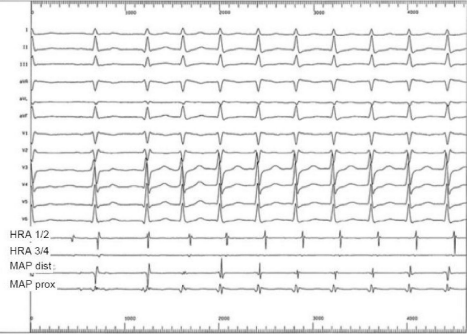

No eletrograma abaixo, o paciente apresentou dois episódios distintos de taquicardia que necessitou de terapia. É correto afirmar que:

Legenda: HRA = eletrodos 1 e 2, 3 e 4 atriais altos; MAP = cateter de ablação no ventrículo.